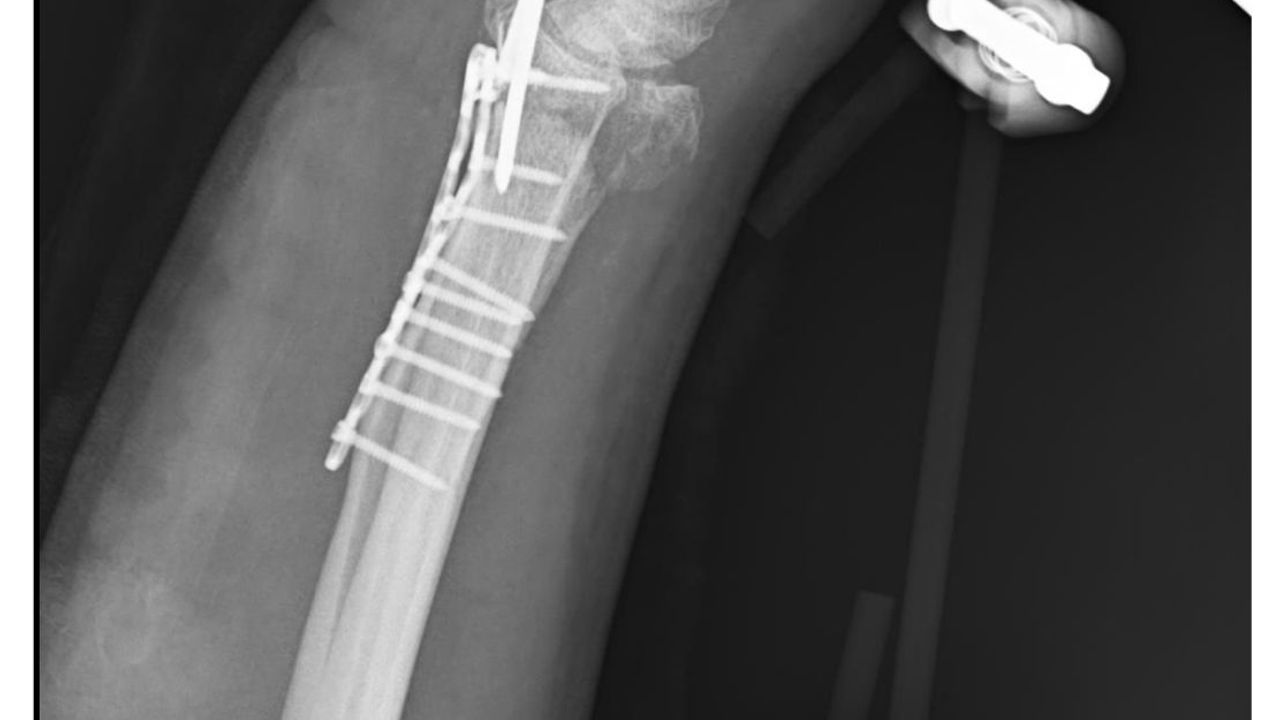

Olay, geçen 29 Aralık'ta Yeşilbayır Mahallesi'nde meydana geldi. Yasin Arslantaş, sabah işe gitmek için çıktığı evinin önünde 9 sokak köpeğinin saldırısına uğradı. Arslantaş, üzerine gelen köpekleri görünce kaçmaya başladı. Arslantaş, peşinden koşup bacaklarından ısırmaya çalışan köpeklerden kurtulup yol kenarında park halindeki kamyonetin kasasına çıktı. Bu sırada dengesini kaybedip düşen Arslantaş, yaralandı. 112 Acil Servis'i arayarak yardım isteyen Arslantaş, ambulansla hastaneye kaldırıldı. Sağ kolunda bilek kısmında parçalı kırık oluşan Arslantaş, ameliyat edilip, tedavisi tamamlandıktan sonra taburcu edildi. Köpeklerin saldırması ve Arslantaş'ın koşarak kaçması, güvenlik kamerasına yansıdı.

Kolu askıda olan ve kontrolleri süren Arslantaş, 'Sabah işe gitmek için evden çıktığım sırada arkamdan 9 köpek geldi. Köpekler saldırgandı. Aracın hemen yanında pikap vardı. Köpekler saldırgan şekilde koştu peşimden, kaydım, düştüm. Doktorlar, bilekteki kemiğin parçalı kırık olması nedeniyle tam iyileşmenin zor olduğunu belirtti. Yanı sıra his ve hareket kaybı yaşanabileceği ifade ettiler. Yaklaşık 3-3,5 saat süren ameliyatın ardından 2 ay kadar fizik tedavi görmem gerektiği söylendi' dedi.